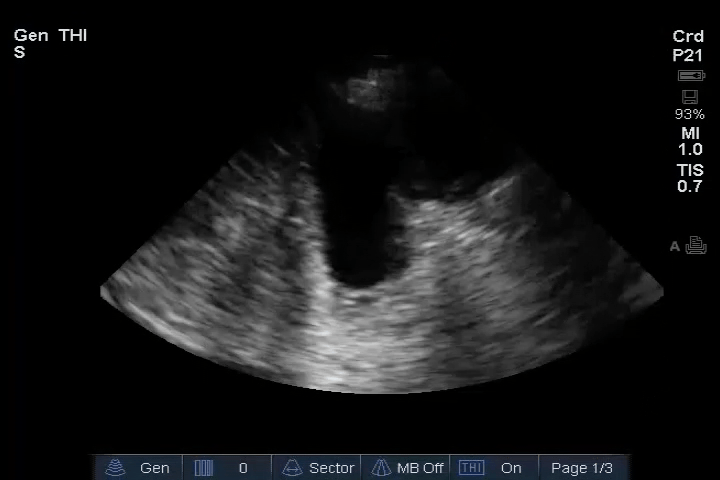

03_Lung_Posterior_axillary_Right – pleura effusion

04_Lung_Posterior_axillary_Left – pleura effusion